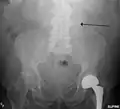

three white arrows pointing to an enlargement of the abdominal aorta

CT reconstruction image of an abdominal aortic aneurysm (white arrows)